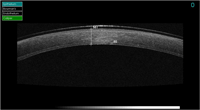

Figura 1). También se pueden estudiar adelgazamientos corneales como el queratocono (

Figura 2), opacidades corneales estromales y su profundidad, patologías asociadas al LASIK (

Figura 2. Vemos la ectasia de un queratocono.